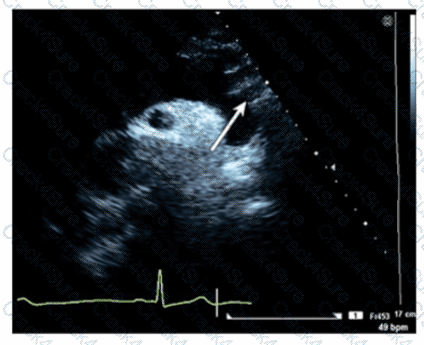

Which artery is identified by the arrow on this image?

Which phase of the cardiac cycle is indicated by the arrow on this image?